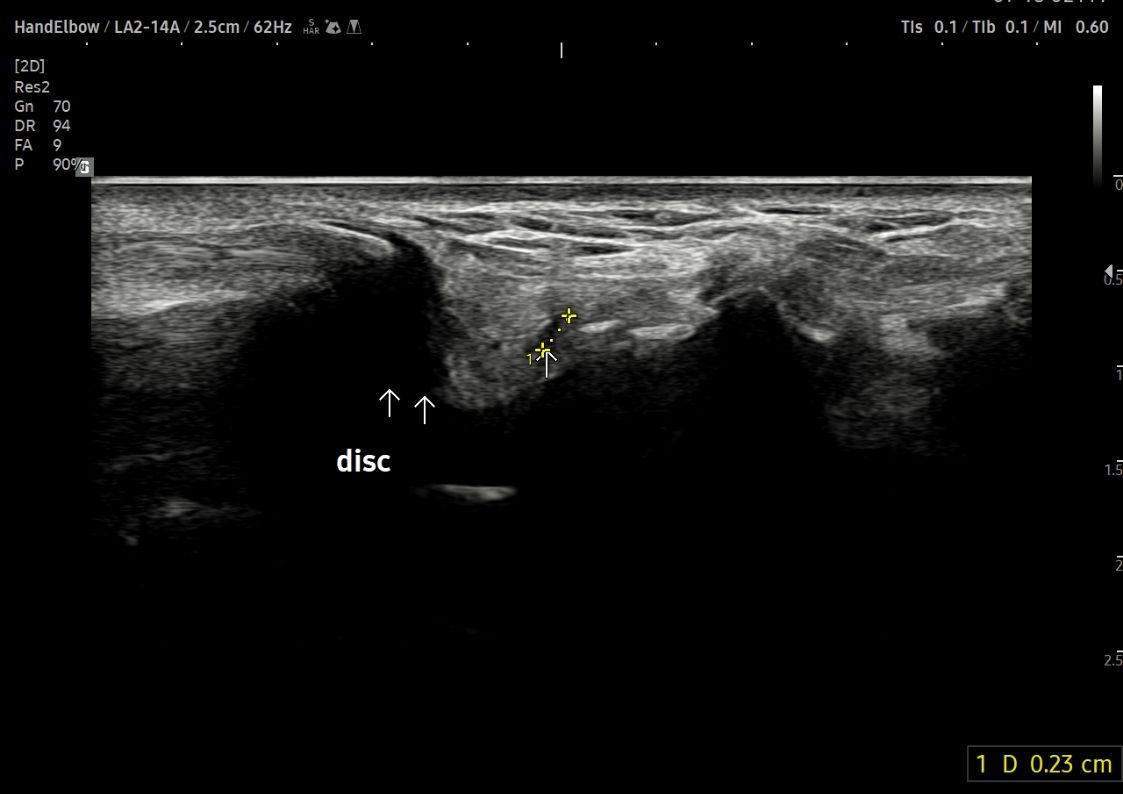

- 치료기간 : 25 . 6 . 9 ~ 25 . 10 .27

- 치료횟수 : 4 사이클(20) 회

치료전

치료 후

힘줄 두께 감소 및 전체적인 파열 부위 축소 & 골극 감소

-> 검사상 파열은 여전히 있지만 운동 이후에도 통증이 크게 없어서 치료 종료 후 3~4주정도 텀 두고 관찰 예정